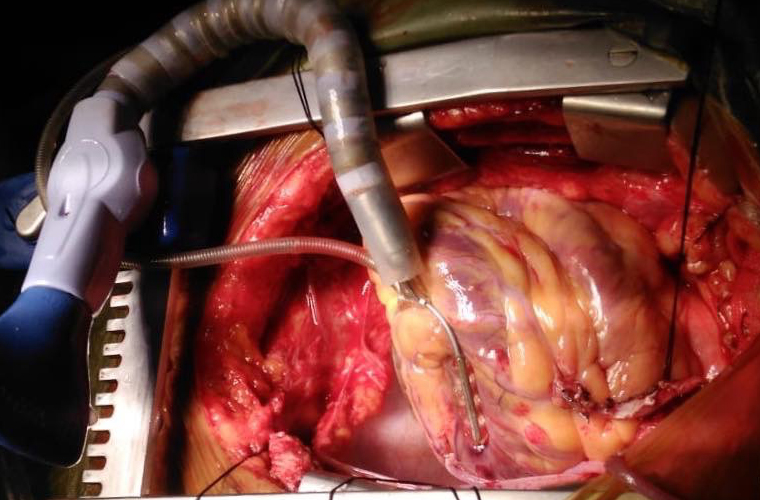

Dr.DineshShanmugaSundaram is specialized himself in each & every part of Cardiovascular & Thoracic Surgery both in Adult & Paediatric or Congenital Heart Diseases. He is both an ethical & academic surgeon,changed the trend in Cardiac Surgery to fast & safe level, as prolonged procedures in Cardiac Surgery increases postoperative complications. We aim at decreasing perioperative complications to the maximal level. Read More